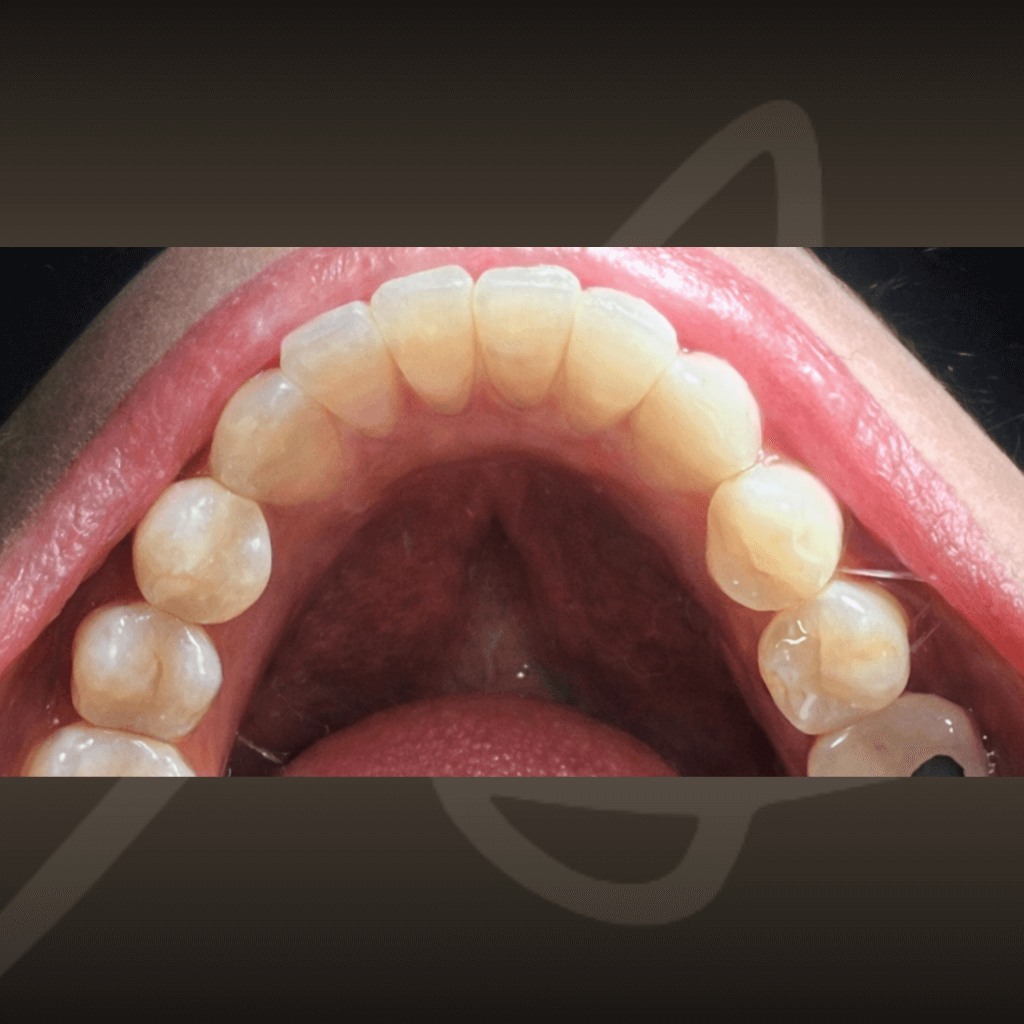

Ортодонтията не е само въпрос на подредба. Правилното лечение подобрява захапката, речта и създава стабилна основа за дългосрочно дентално здраве. Независимо от възрастта, ортодонтското лечение може да допринесе за по-добър функционален баланс и по-лесна поддръжка на зъбите във времето.